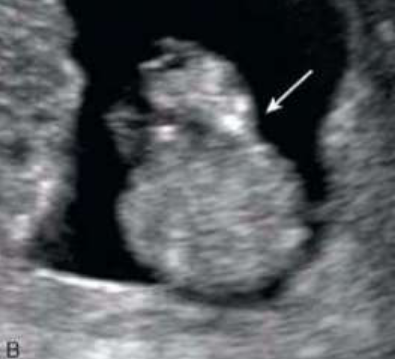

O mioma (leiomioma) uterino é um tumor benigno, muito comum, que pode acometer

até 70% das mulheres com 50 anos de idade. Para sistematizar a descrição dos miomas, foi criada a classificação da FIGO (Federação Internacional de Ginecologia e Obstetrícia) juntamente com o grupo MUSA (Morphological Uterus Sonografic Assessment), utilizando estes parâmetros classifique o nódulo abaixo: